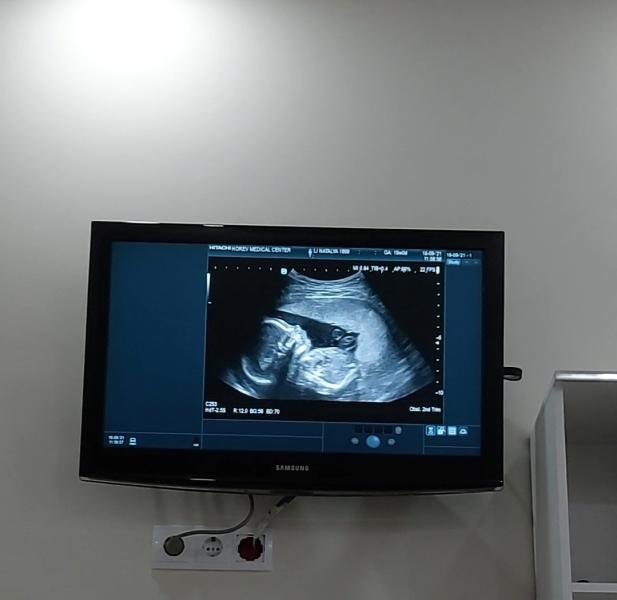

Но с хорошей новостью, ходила на большой скриниг все хорошо с ребенком, уже 20 недель как нам🥰